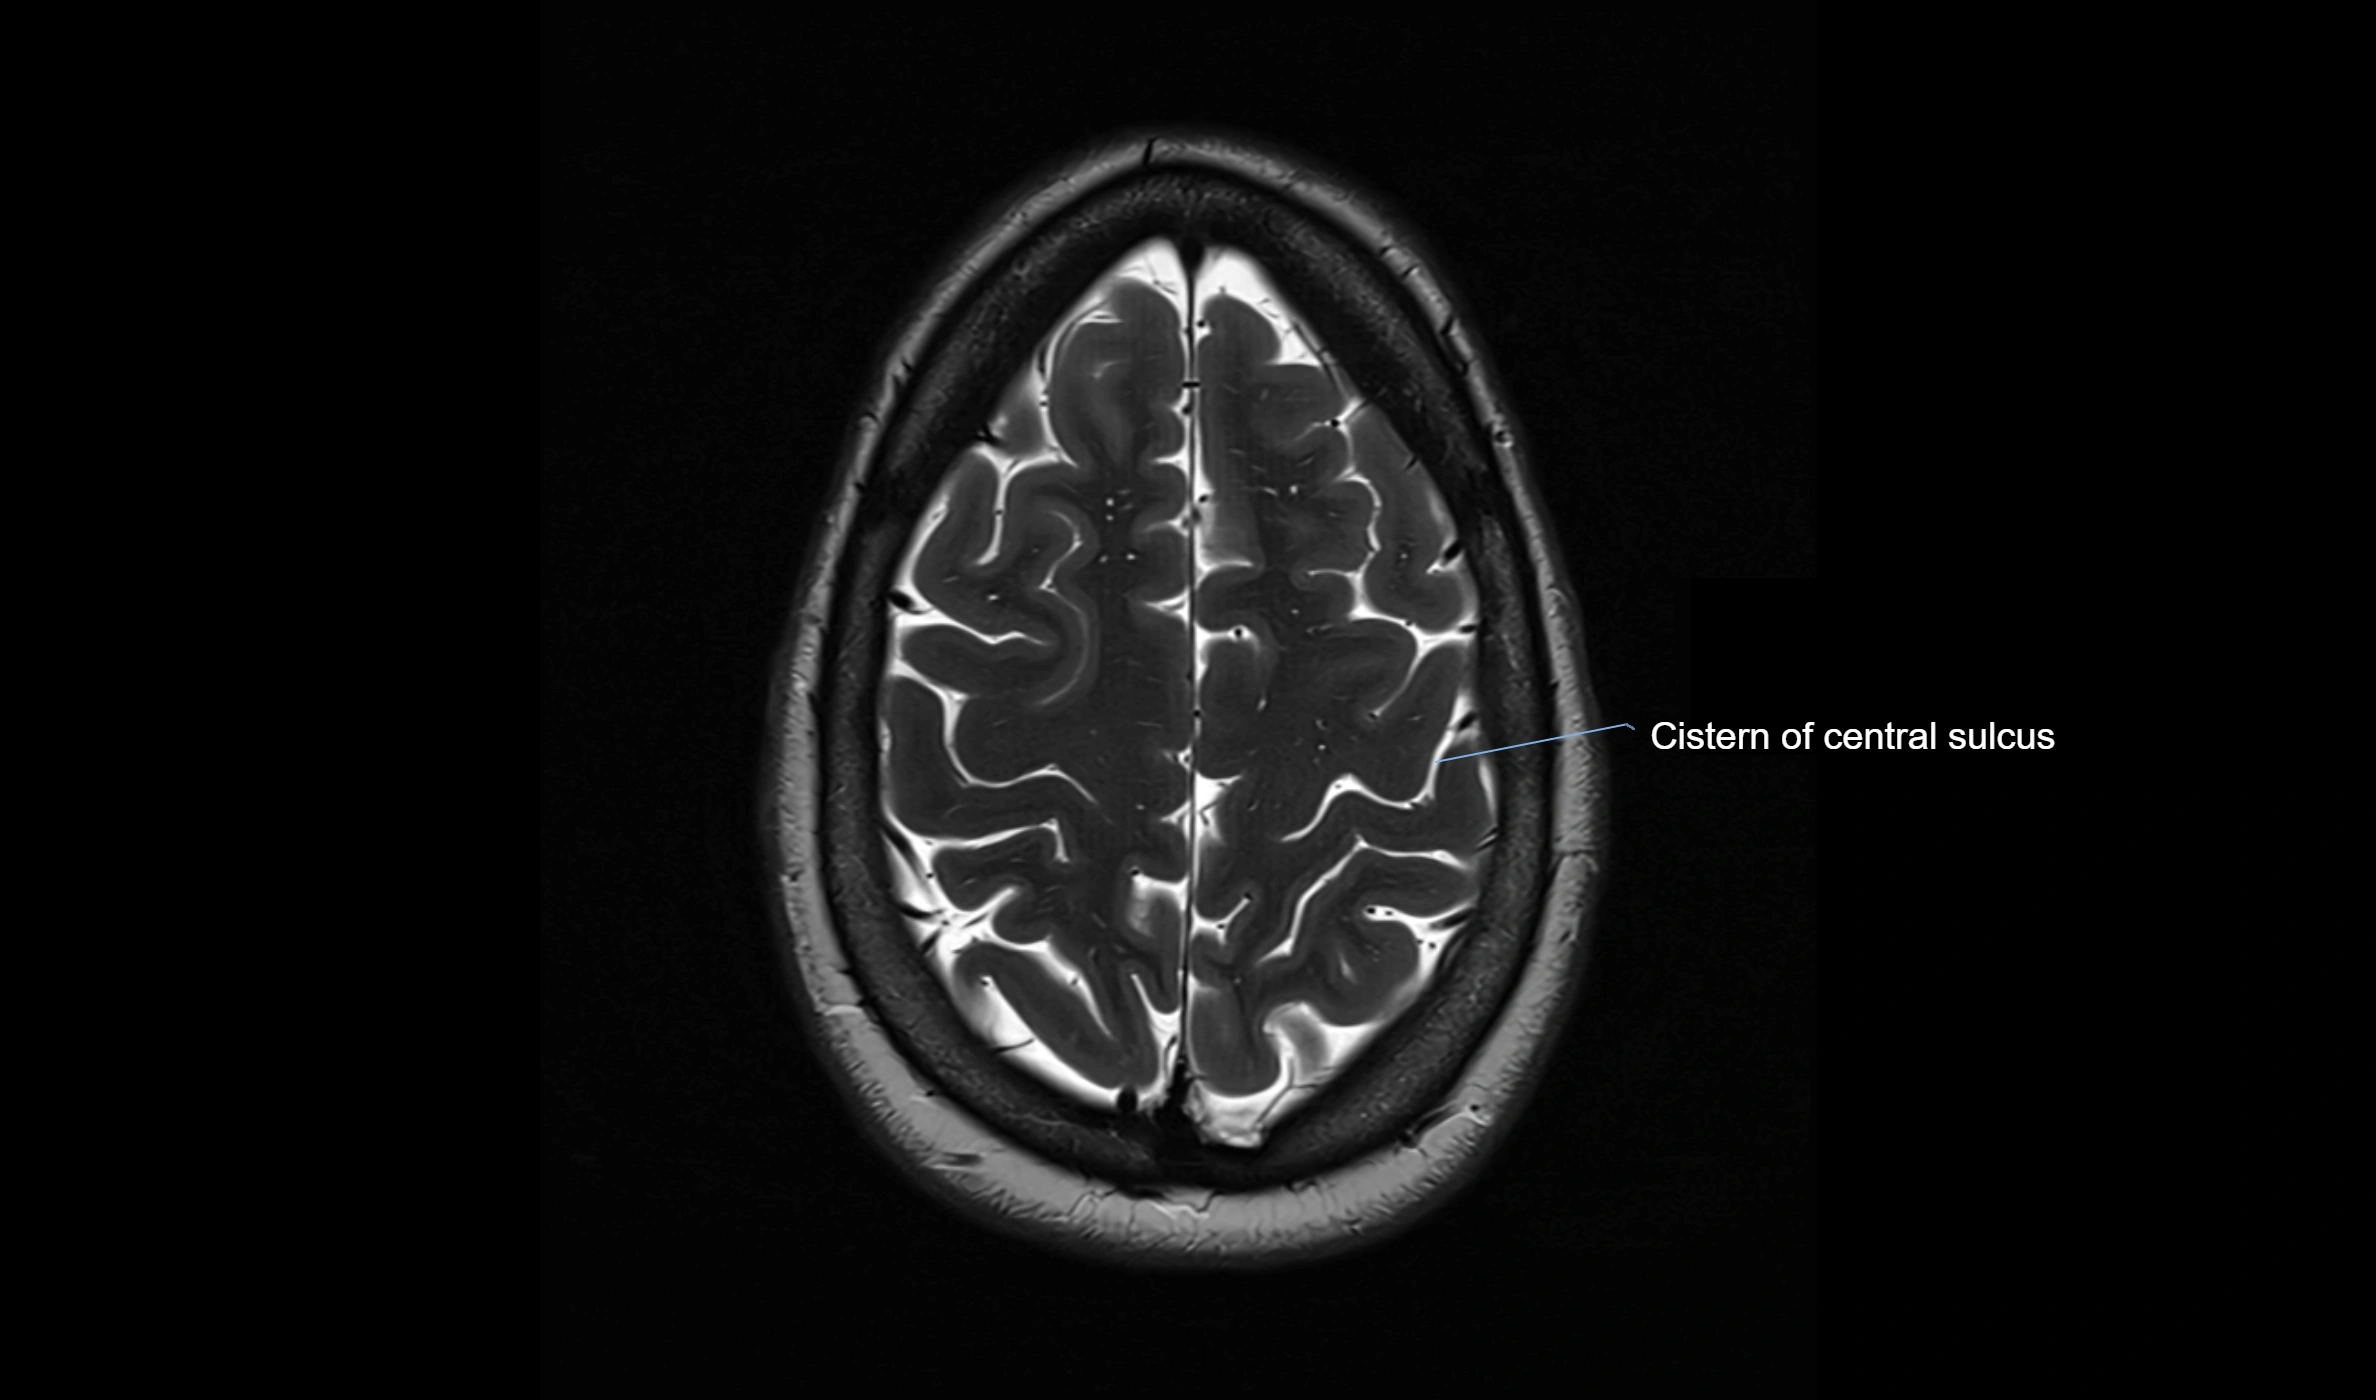

MRI images

image